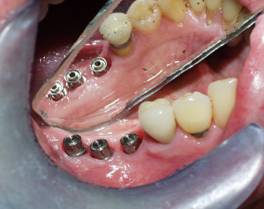

Replace Two Lower molars (Three Implants Two Teeth)

Mirror reflection

-Before

Dental Implant